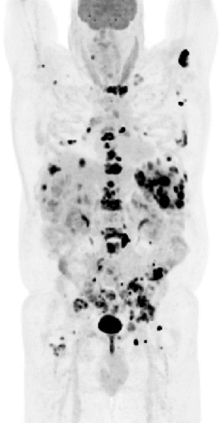

We investigated the imaging performance of a fast convergent ordered-subsets algorithm with subiteration-dependent preconditioners (SDPs) for positron emission tomography (PET) image reconstruction. In particular, we considered the use of SDP with the block sequential regularized expectation maximization (BSREM) approach with the relative difference prior (RDP) regularizer due to its prior clinical adaptation by vendors. Because the RDP regularization promotes smoothness in the reconstructed image, the directions of the gradients in smooth areas more accurately point toward the objective function's minimizer than those in variable areas. Motivated by this observation, two SDPs have been designed to increase iteration step-sizes in the smooth areas and reduce iteration step-sizes in the variable areas relative to a conventional expectation maximization preconditioner. The momentum technique used for convergence acceleration can be viewed as a special case of SDP. We have proved the global convergence of SDP-BSREM algorithms by assuming certain characteristics of the preconditioner. By means of numerical experiments using both simulated and clinical PET data, we have shown that our SDP-BSREM substantially improved the convergence rate, as compared to conventional BSREM and a vendor's implementation as Q.Clear. Specifically, in numerical experiments with a synthetic brain phantom, both proposed algorithms outperformed the conventional BSREM by a factor of two, while in experiments with clinical whole-body patient PET data (with and without time-of-flight information), the SDP-BSREM algorithm converged 35\%-50\% percent faster than the commercial Q.Clear algorithm.